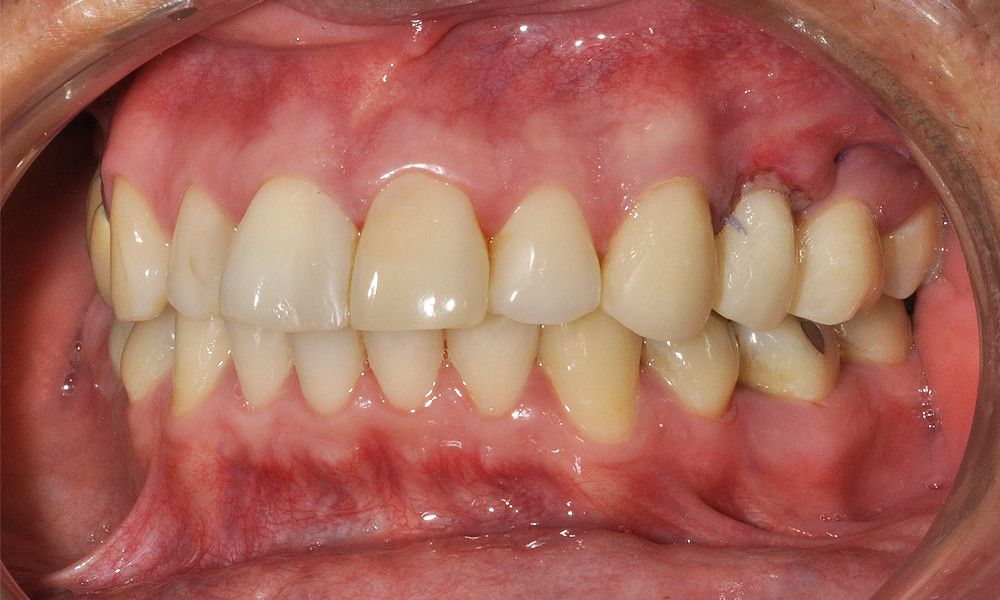

Reporte del Caso: Paciente sexo masculino, 36 años, con diagnóstico de esquizofrenia y trastorno bipolar en tratamiento. Consulta por el recambio de dos prótesis fijas plurales (PFP) de reemplazo de dientes 4 y 13 con pilares en piezas 3, 5, 12 y 14 mediante rehabilitaciones unitarias de los dientes pilares y reemplazo mediante implantes en zonas edéntulas.

El estudio imagenológico evidencia una pérdida ósea severa en altitud y grosor, situación que complejiza la colocación de un implante. Se analizan alternativas de tratamiento y se opta por una vestibuloplastía mediante autoinjerto conectivo de mucosa palatina que se reposiciona sobre la zona del defecto óseo. Además se realiza retratamiento de ambas PFP, ahora en zirconia, por motivos estéticos y oclusales. Se realizan controles posteriores para evaluar la respuesta gingival a la vestibuloplastía.

Conclusiones: La ausencia de un diente no siempre es indicativo de implante. El tratamiento elegido debe tener las menores complicaciones, el mínimo daño, el máximo beneficio y un costo económico de acuerdo a la realidad del paciente. La PFP de zirconio y la vestibuloplastía son alternativas de tratamiento efectivas para la resolución de defectos óseos por ausencia dentaria en la cavidad oral.